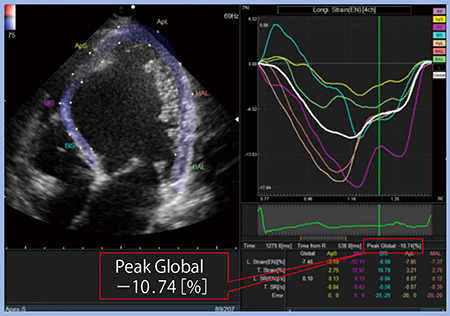

“2D Tissue Tracking”は,スペックルトラッキングをきわめて簡便に解析し,Global Longitudinal Strain(GLS)を算出できる。症例2を解析すると,収縮および拡張の間隔にバラツキが見られ,GLSも−10.74%と低値であり(図4),左室機能が低下していることがわかる。

図4 2D Tissue Tracking(症例2)